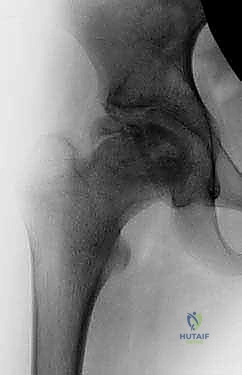

Clinical & Radiographic Imaging